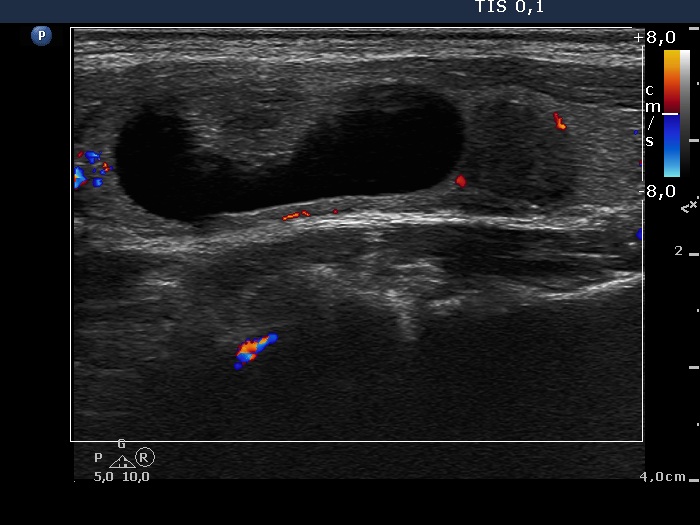

Ultrasonography. The thyroid was echonormal. There was a spongiform-type cyst in the right lobe. The small cystic areas of the lesion exhibited posterior back wall enhancement. The vascularization was scanty. Compared with the former examination, the nodule remained just as large. There was another nodule in the left lobe which was not described on previous ultrasound report. This lesion was hypoechogenic, presented hyperechogenic granules and showed taller-than-wide sign.